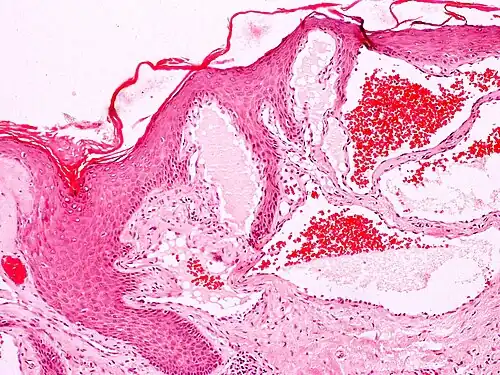

Angiokeratomas characteristically have large dilated blood vessels in the superficial dermis and hyperkeratosis (overlying the dilated vessels).

Scrotal angiokeratoma (Fordyce type); dilated cavernous capillaries, acanthosis